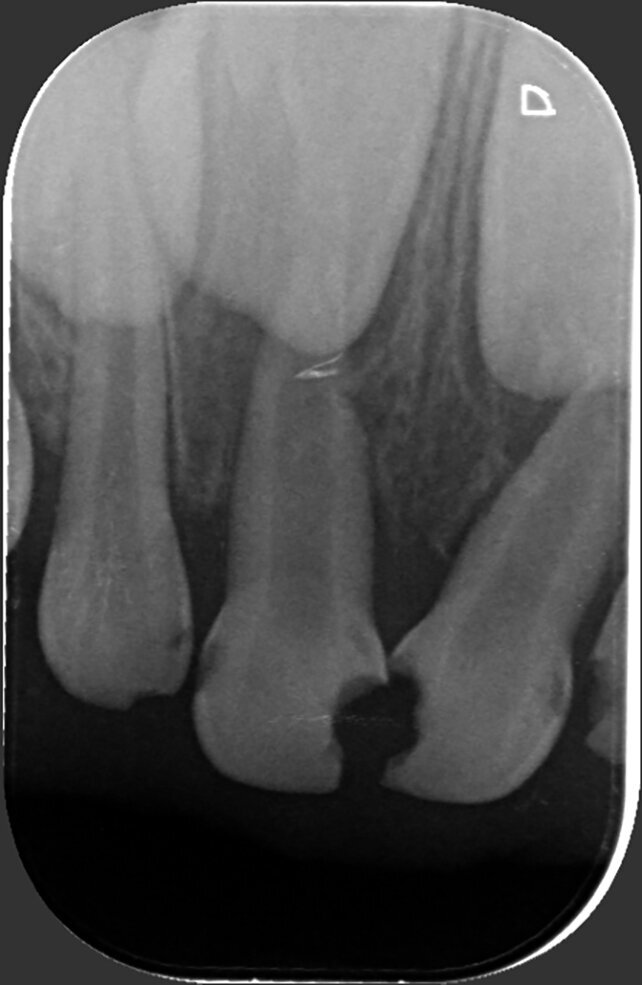

A 4-year-old girl was referred to the Children’s Dental Center in Gurgaon in India with the complaint of painful teeth when eating and the presence of unsightly maxillary anterior teeth. Clinical examination showed large carious lesions in the maxillary anterior teeth (Fig. 1). A radiographic examination showed pulpal involvement of caries in teeth #51 and 61 (Fig. 2).

Fig. 2: Radiographic examination revealed pulpal involvement of caries in 51 and 61.